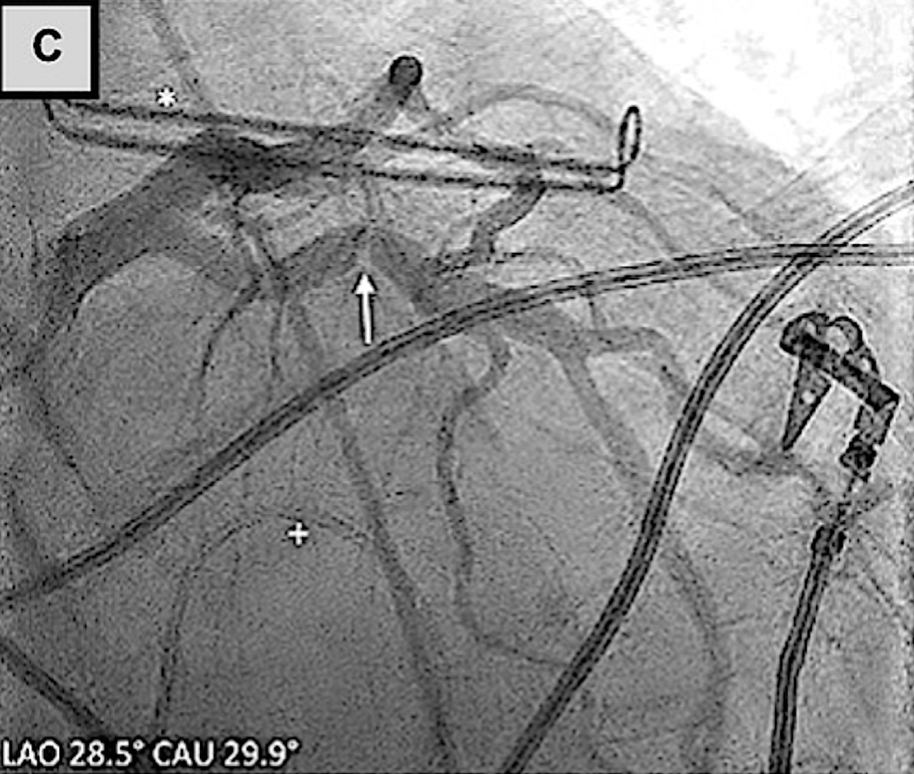

AtriClip左心耳封堵术与左冠状动脉的关系

(A)术前冠状动脉造影显示回旋支狭窄不显著。(B、C)使用AtriClip装置进行左心耳封堵术后,冠状动脉造影证实回旋支存在显著狭窄。(D)回旋支经皮冠状动脉介入治疗后,冠状动脉造影显示血管造影结果良好